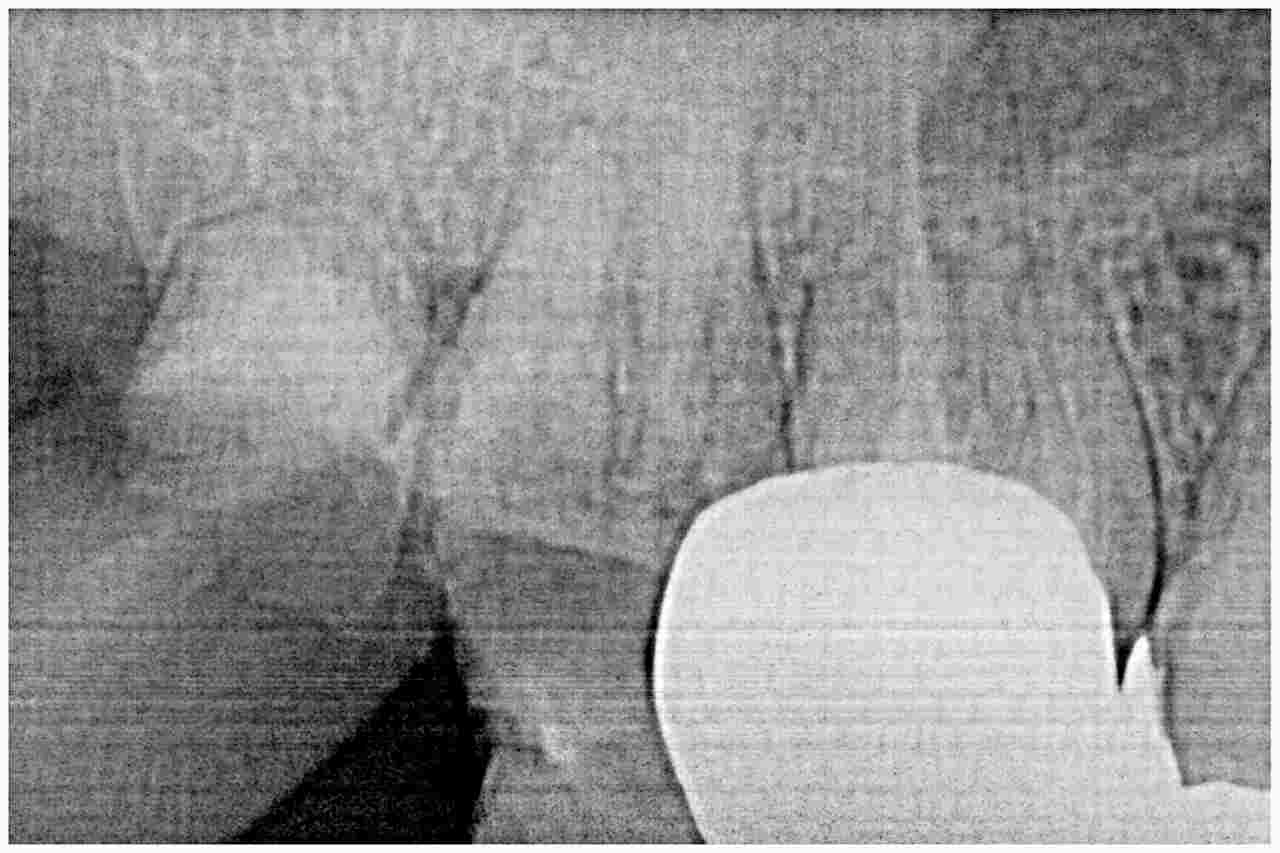

デンタルレントゲンではこのような状態になります